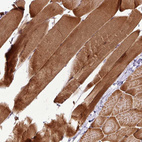

Immunohistochemical staining of human skeletal muscle shows moderate cytoplasmic positivity in myocytes.